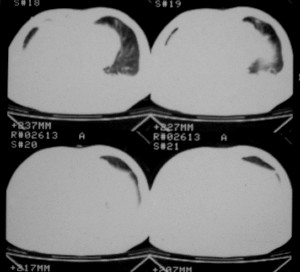

肝及右肾转移瘤,双侧胸水

右肾及肝内多发转移瘤,胸水。

1、右肺癌术后改变。2、双侧胸水、腹水。3、多发性肝囊肿,右侧肾囊肿。